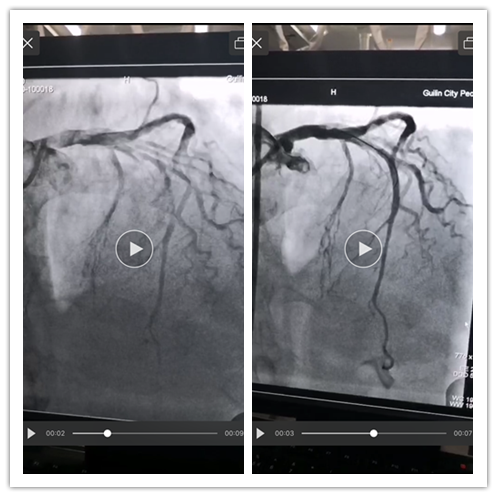

上午12时26分,由急诊科李祖华主治医师、李秋护师组成的院前溶栓小组,携带装有心梗溶栓药物的冷链箱到达莲花乡卫生院。此时患者胸痛较前加重,并伴有大汗淋漓。院前溶栓小组复查心电图,确诊为“急性广泛前壁ST段抬高型心肌梗死”,有明确的静脉溶栓指征,无明显禁忌症。经过与家属进行沟通后,家属签字同意静脉溶栓治疗,院前溶栓小组在返程的急救车上,完成了溶栓治疗的全过程,并安全返回恭城分院,经胸痛绿色通道,绕行急诊科直接送入心内科CCU病房。溶栓2小时后,患者胸痛症状明显缓解,生命体征正常,复查心电图提示病变血管已溶通,并于晚上9时转入上级医院,行冠脉造影术提示左前降支次全闭塞,证实了溶栓的成功。目前患者正在接受进一步观察及治疗,预计术后2-3天即可康复出院。

溶栓影像